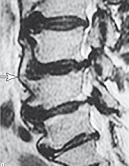

На МРТ № 4 наблюдается межпозвонковый диск в начальной стадии развития дегенеративно-дистрофического процесса.

На МРТ № 5 наблюдается межпозвонковый диск на более поздней стадии развития дегенеративно-дистрофического процесса.